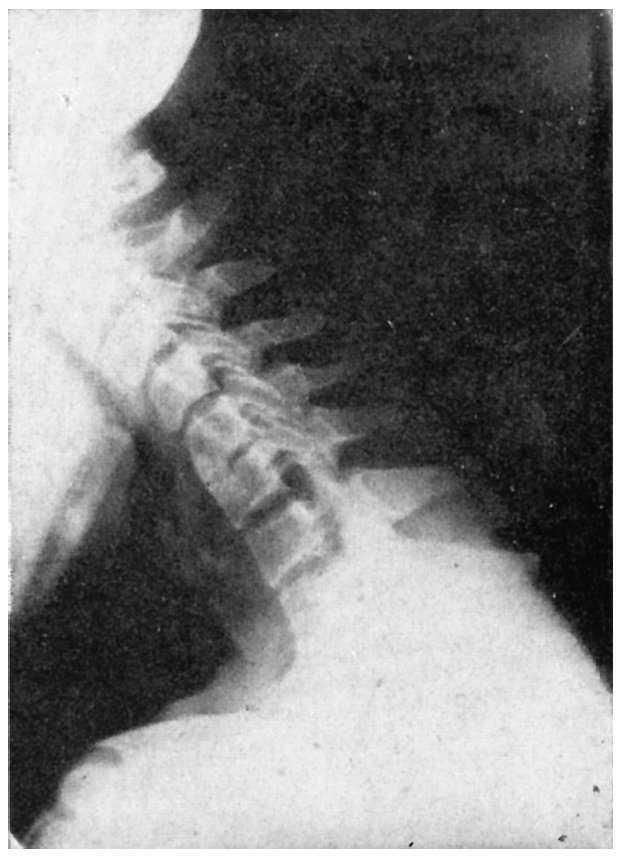

Hay que hacer radiografías de tipo funcional, es decir, de perfil en flexión y en extensión máximas, observando si además de una discosis hay hipermovilidad o inestabilidad en la columna cervical que se estudia.

La lesión es evidente en los discos con disminución evidente de su altura, con reacción ósea que ensancha las caras superior e inferior de las vértebras afectadas; los osteofitos se observan tanto en el borde anterior como en el posterior, algunas veces con evidente protusión hacia el conducto medular. Los discos más habitualmente afectados son el 5.o, 6.o, y el 7.o; también se afecta el 4.o, y 5.o, pero menos. Los discos afectados a veces son dos o tres, y a veces es sólo uno.

El síndrome clínico, lo mismo puede existir por irritación nerviosa o cálculo-nerviosa en el agujero de conjunción, por un osteofito pósterolateral o por una hernia discal media o lateral, así como por una inestabilidad vertebral cuyo exceso de movilidad provoca también un síndrome cervical. Por la tanto, en la observación radiológica tanto valor puede tener la discosis como la inestabilidad de alguna vértebra (fig. 2).

Figura 2.Causas de irritación de los nervios raquídeos.